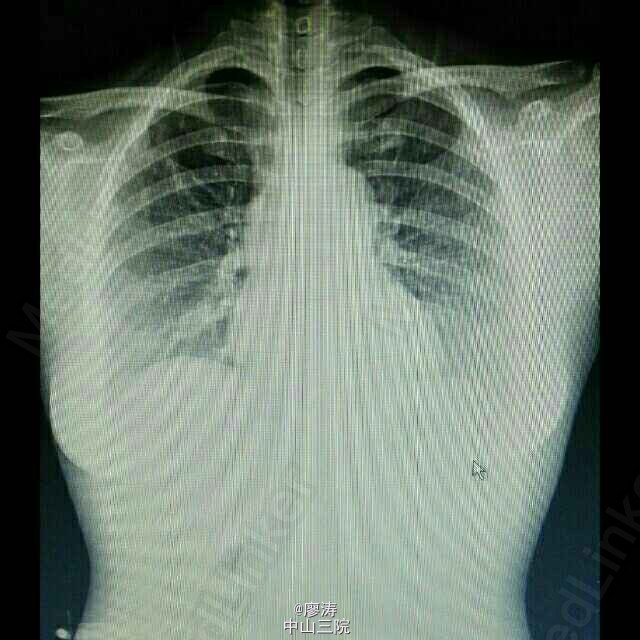

患者女,29岁,因尿毒症入院,欲行肾移植手术治疗,术前完善相关检查。肾移植术前检查与其他手术术前检查类似,包括血型,血常规,凝血功能,生化全套,术前筛查8项,心电图,胸前,腹部彩超,甲状腺彩超,乳腺彩超(女性),盆腔部位彩超,因为肾移植手术部位选择在髂窝,所以双侧髂血管彩超检查也是很重要的一项,以下图片为部分检查报告单。